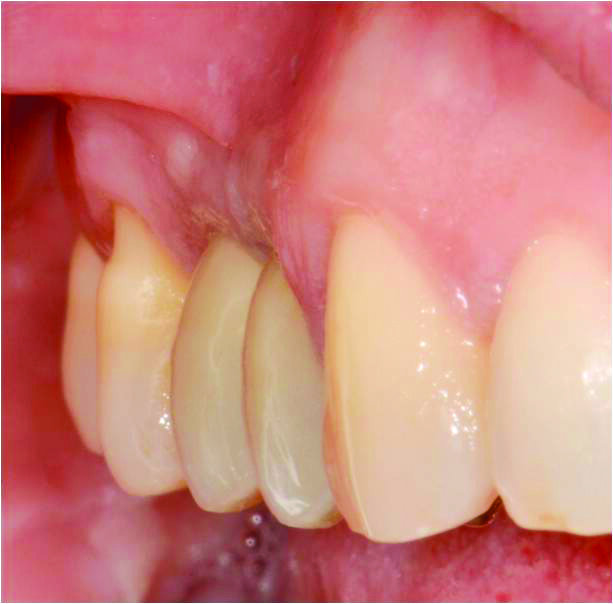

Dopo una fase di maturazione di 3 mesi è stato osservato un significativo aumento sia dello spessore che dell’altezza della mucosa cheratinizzata perimplantare. La maturazione dei tessuti evidenzia come l’inserzione del frenulo vestibolare sia migrata apicalmente rispetto alla sua posizione originale (Figg. 9, 10).

Figg. 9, 10_Dopo una fase di maturazione di 3 mesi, è stato osservato un significativo aumento del volume dei tessuti molli buccali e un miglioramento del deficit verticale dei tessuti molli.